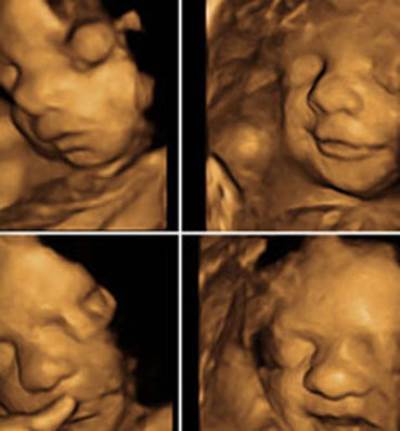

توصلت دراسة طبية إلى تطوير اختبار بول جديد، اعتمادا على عينات بول صغيرة، لديه القدرة على تقييم مراحل نمو الجنين وتسجيل توصيات صحية فيما يتعلق بالجنين.

وتعد التشوهات فى النمو الطبيعى للجنين وانخفاض وزنه عند الولادة من أهم عوامل الخطر للأمراض المزمنة فى وقت لاحق من حياته، بما فى ذلك مرض السكر النوع الثانى والبدانة.

وأوضح الباحثون أن المواد والعلامات الأيضية التى يتم تشخيصها فى بول الأم تظهر الإشارات على وزن الطفل عند الولادة، فضلا عن إعطائه اقتراحات لتغيير نمط الحياة للمساعدة فى الحفاظ على حجم الجنين.